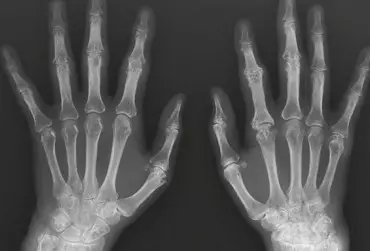

Dolegliwości bólowe w obrębie kończyny górnej mogą mieć różną przyczynę, dlatego tak ważna jest diagnostyka różnicowa. W ustaleniu prawidłowego rozpoznania pomocne jest tradycyjne badanie radiologiczne, które pozwala na wykrycie wielu patologii, takich jak urazy, zmiany zwyrodnieniowe, przeciążeniowe, choroby metaboliczne, zapalne i nowotwory, choć ma też swoje ograniczenia.